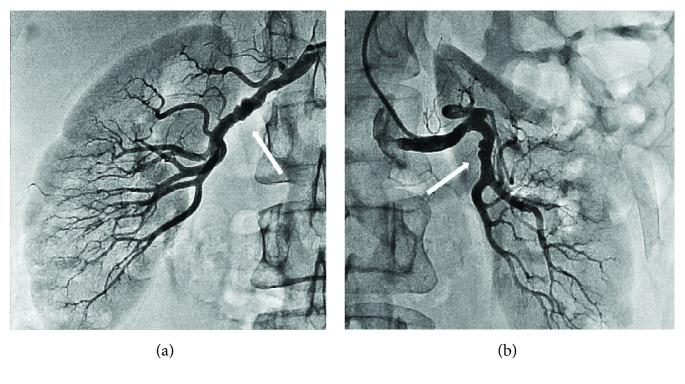

We report a case of a patient with acute MI caused by SCAD with marked progression of dissection within 4 days and spontaneous healing in 2 months. Fibromuscular dysplasia (FMD) of the arteries is an associated condition of SCAD that was found in our patient.

我们报告一例由SCAD引起的急性心肌梗死患者,其夹层在4天内显著进展,2个月内自发愈合。动脉纤维肌发育不良(FMD)是该患者所发现的与SCAD相关的一种病症。